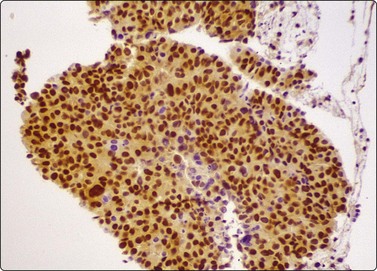

image

Fig. 8.2 Mesothelial cells

Monolayered sheet of cells showing ‘spongiotic’ separation of individual cells within the sheet (Pap, LP).

Mesothelium can be easily distinguished from bronchiolar epithelium. It is seen as various-sized, flat, monolayered sheets; there is usually more cell separation than in bronchiolar epithelium, which sometimes gives a sponge-like appearance. The cells appear to be joined by intercellular bridges similar to those of squamous epithelium in histological sections. (Fig. 8.2). Reactive mesothelium can appear atypical and be misinterpreted as neoplastic.